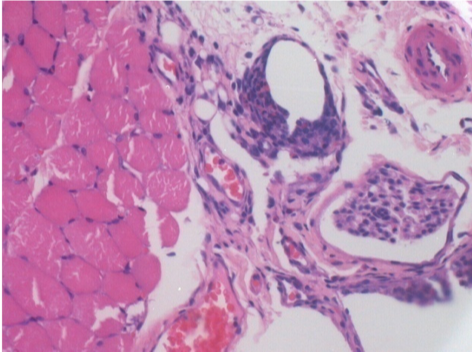

П-90днів-ПШ-200X

П-210днів-ПШ-200X

П-210днів-ПШ-400X